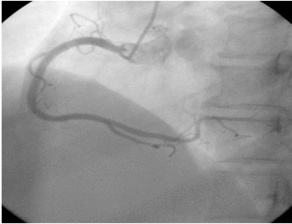

La coronarographie consiste à enfiler une aiguille dans l'artère fémorale, à envoyer un tube jusqu'à l'emplacement de l'artère coronaire, à appliquer un produit de contraste iodé et à montrer l'artère coronaire, ce qui permet de diagnostiquer les maladies congénitales de l'artère coronaire, l'athérosclérose, les anévrismes, les malformations artérielles et d'autres maladies, dont la plupart sont des athéroscléroses qui entraînent un rétrécissement de la lumière. Le degré de sténose peut être évalué et, dans le cas d'une sténose grave, avec infarctus du myocarde, un stent peut être directement mis en place pour ouvrir la lumière rétrécie et rétablir le flux sanguin à des fins thérapeutiques.

La cardiographie fait référence à l'angiographie coronarienne. Le processus général consiste à pratiquer une petite ouverture dans l'artère radiale ou fémorale du premier examinateur, à insérer un fin cathéter à partir de l'incision, à suivre la direction de l'artère, à pénétrer profondément dans l'artère coronaire, puis à injecter un produit de contraste, de sorte que l'imagerie de l'artère coronaire puisse être claire sur la maladie coronarienne et ses branches, sur le rétrécissement du site et sur le degré de la maladie coronarienne, ce qui permet de diagnostiquer la maladie coronarienne. "l'étalon-or". Ci-dessous, nous abordons ensemble trois questions :

La procédure de base de la cardiographie consiste à placer un cathéter par une ponction dans l'artère radiale (au niveau du poignet) ou l'artère fémorale (à la base de la cuisse) et à utiliser un fil-guide pour guider le cathéter de manière rétrograde dans le cœur ou les vaisseaux sanguins importants autour du cœur (aorte, artères coronaires), où il est injecté avec un produit de contraste, qui est ensuite utilisé pour rendre la structure des cavités cardiaques ou des vaisseaux sanguins importants autour du cœur visible sous l'effet des rayons X.